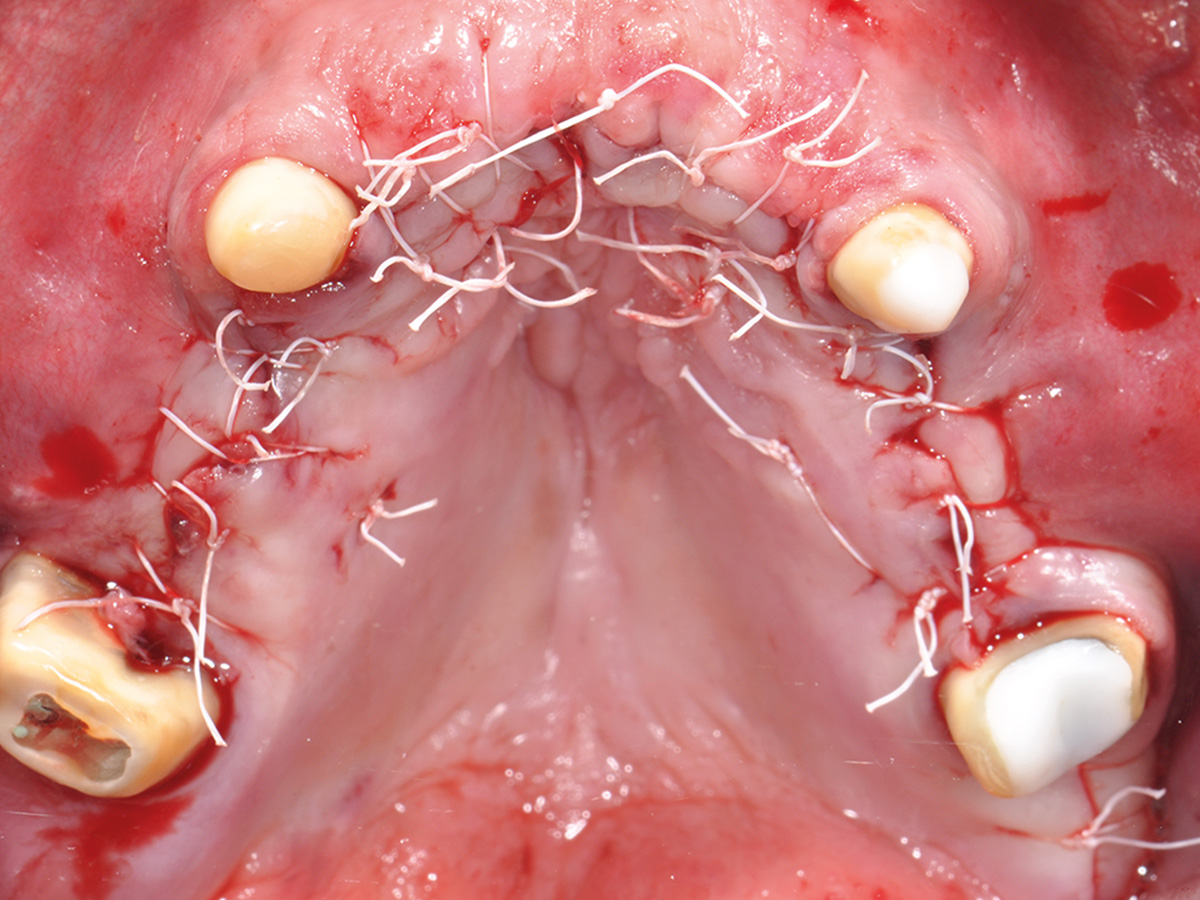

Prinzipien und Konzepte der Knochenaugmentation im Kieferbereich werden logisch aufeinander aufgebaut. Anhand dieser Grundstruktur befähigt der Kurs die Teilnehmer, klinische Situationen fundiert zu analysieren und selbst die logischen chirurgischen Schritte – vom Weichgewebemanagement bis zum Knochenhandling – für die Augmentation abzuleiten.

Im Anschluss werden am Tiermodell alle für eine vorhersehbare Augmentation notwendigen Techniken im Sinne des „Simplify your Augmentation“ eingeübt. Der Weg führt von der einfachen Membrananwendung über die Bone-Lamina- und Double-Layer-Technik bis zur Bone-Shield-Technik. Das Bone Shield ist eine Evolution der klassischen Schalentechnik und erlaubt es, auch komplexe vertikale und kombinierte Augmentationsfälle

im Rahmen der im Kurs vorgestellten Konzeption sicher zu lösen.

Vermittlung des „Simplify your Augmentation“-Konzeptes und Einüben der Bone-Lamina- und Bone-Shield-Techniken am Tiermodell.